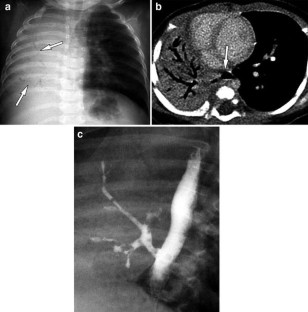

Fig. 1